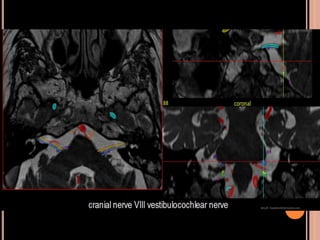

 Schwannomas vestibulares:

Originam-se no conduto auditivo interno; pode se

estender para a cisterna pontocerebelar;

o 5° par (trigêmio): 2° sítio mais acometido;

Achados Clínicos

As primeiras manifestações clínicas geralmente

ocorrem em adultos;

Perda auditiva e tonturas

(lesão do 8° par craniano)

 Schwannomas vestibulares (realce homogêneo

pelo contraste, seria hipo em T1)

SCWHANNOMAS

Pequenas lesões no CAI, bem mais caracterizada

nas aquisições volumétricas(3D CISS);

Aspecto de “sorvete de casquinha” quando lesões

maiores com extensão pontocerebelar;

Hipo em T1 e hiper heterogêneo em T2;

Impregnação pelo Gd homogênea se pequenos e

heterogênea se grandes;